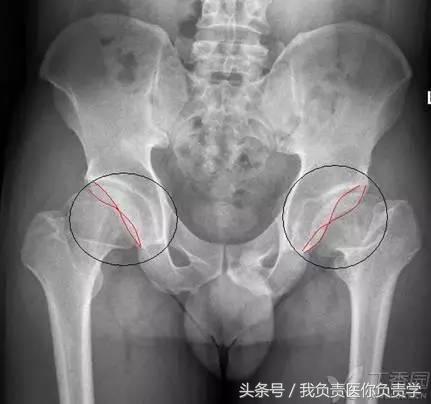

2. Capener 征与骨骺滑脱

在儿童髋关节正位片上,股骨颈内侧缘、股骨头骨骺线、髋臼后壁所围成的高密度三角形称之为「Capener 征 (凯帕诺征)」,当骨骺出现滑脱时,此三角形与健侧对比将变小。